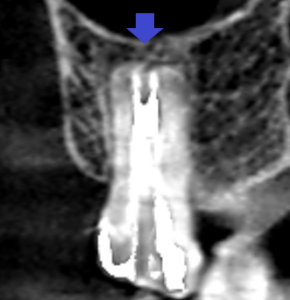

上顎大臼歯の近心頬側根の冠状断のCT画像です。

赤い矢印の先に膿の影がみられます。

青い矢印の先は、近心頬側根の2根管あるうちの未治療の方の根管です。

歯根の先まで石灰化しており、根管がCT画像でも確認出来ませんでした。